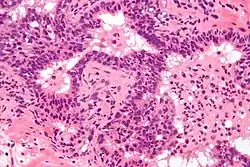

Prostate biopsies are not indicated as the (clinical) features (described above) are diagnostic. The histologic correlate of acute prostatitis is a neutrophilic infiltration of the prostate gland.

Micrograph showing a neutrophilic infiltration of prostatic glands - the histologic correlate of acute prostatitis.